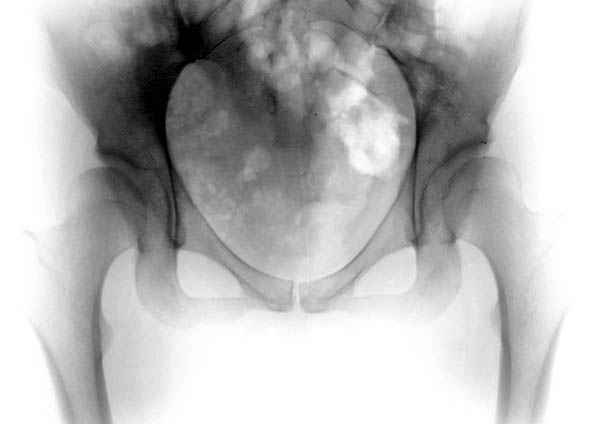

Как раз к обсуждению. Обратилась за косультацией 21-летняя девушка с жалобами на боли в левом тазобедренном суставе. Что можно ей порекомендовать?

coxa.jpg